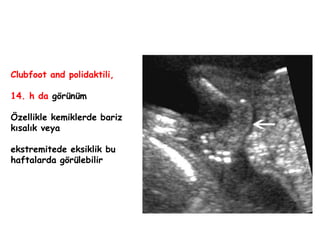

Clubfoot and polidaktili,

14. h da görünüm

Özellikle kemiklerde bariz

kısalık veya

ekstremitede eksiklik bu

haftalarda görülebilir